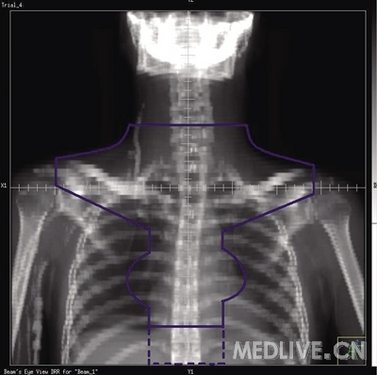

2 纵隔野

肿瘤侵犯范围:纵隔和(或)肺门淋巴结。

靶区定义:纵隔、双侧肺门,双侧锁骨上下区和下颈部。即使无双锁骨上淋巴结受侵,锁骨上淋巴引流区也应常规包括在照射野内(图2)。

上界:颈6锥体上缘。

下界:隆突下5 cm或胸8锥体下缘,或者化疗前肿瘤下界下2 cm。

外界:体中线左右各旁开4~5 cm,双锁骨上外界为肱骨头内缘。

肺门:包括1 cm边缘,若肺门受侵,包括1.5 cm边缘。

HL的主要表现为前上纵隔受侵,小纵隔时,为减少心脏照射,下界至胸8锥体下缘;大纵隔时,下界至胸10锥体下缘。